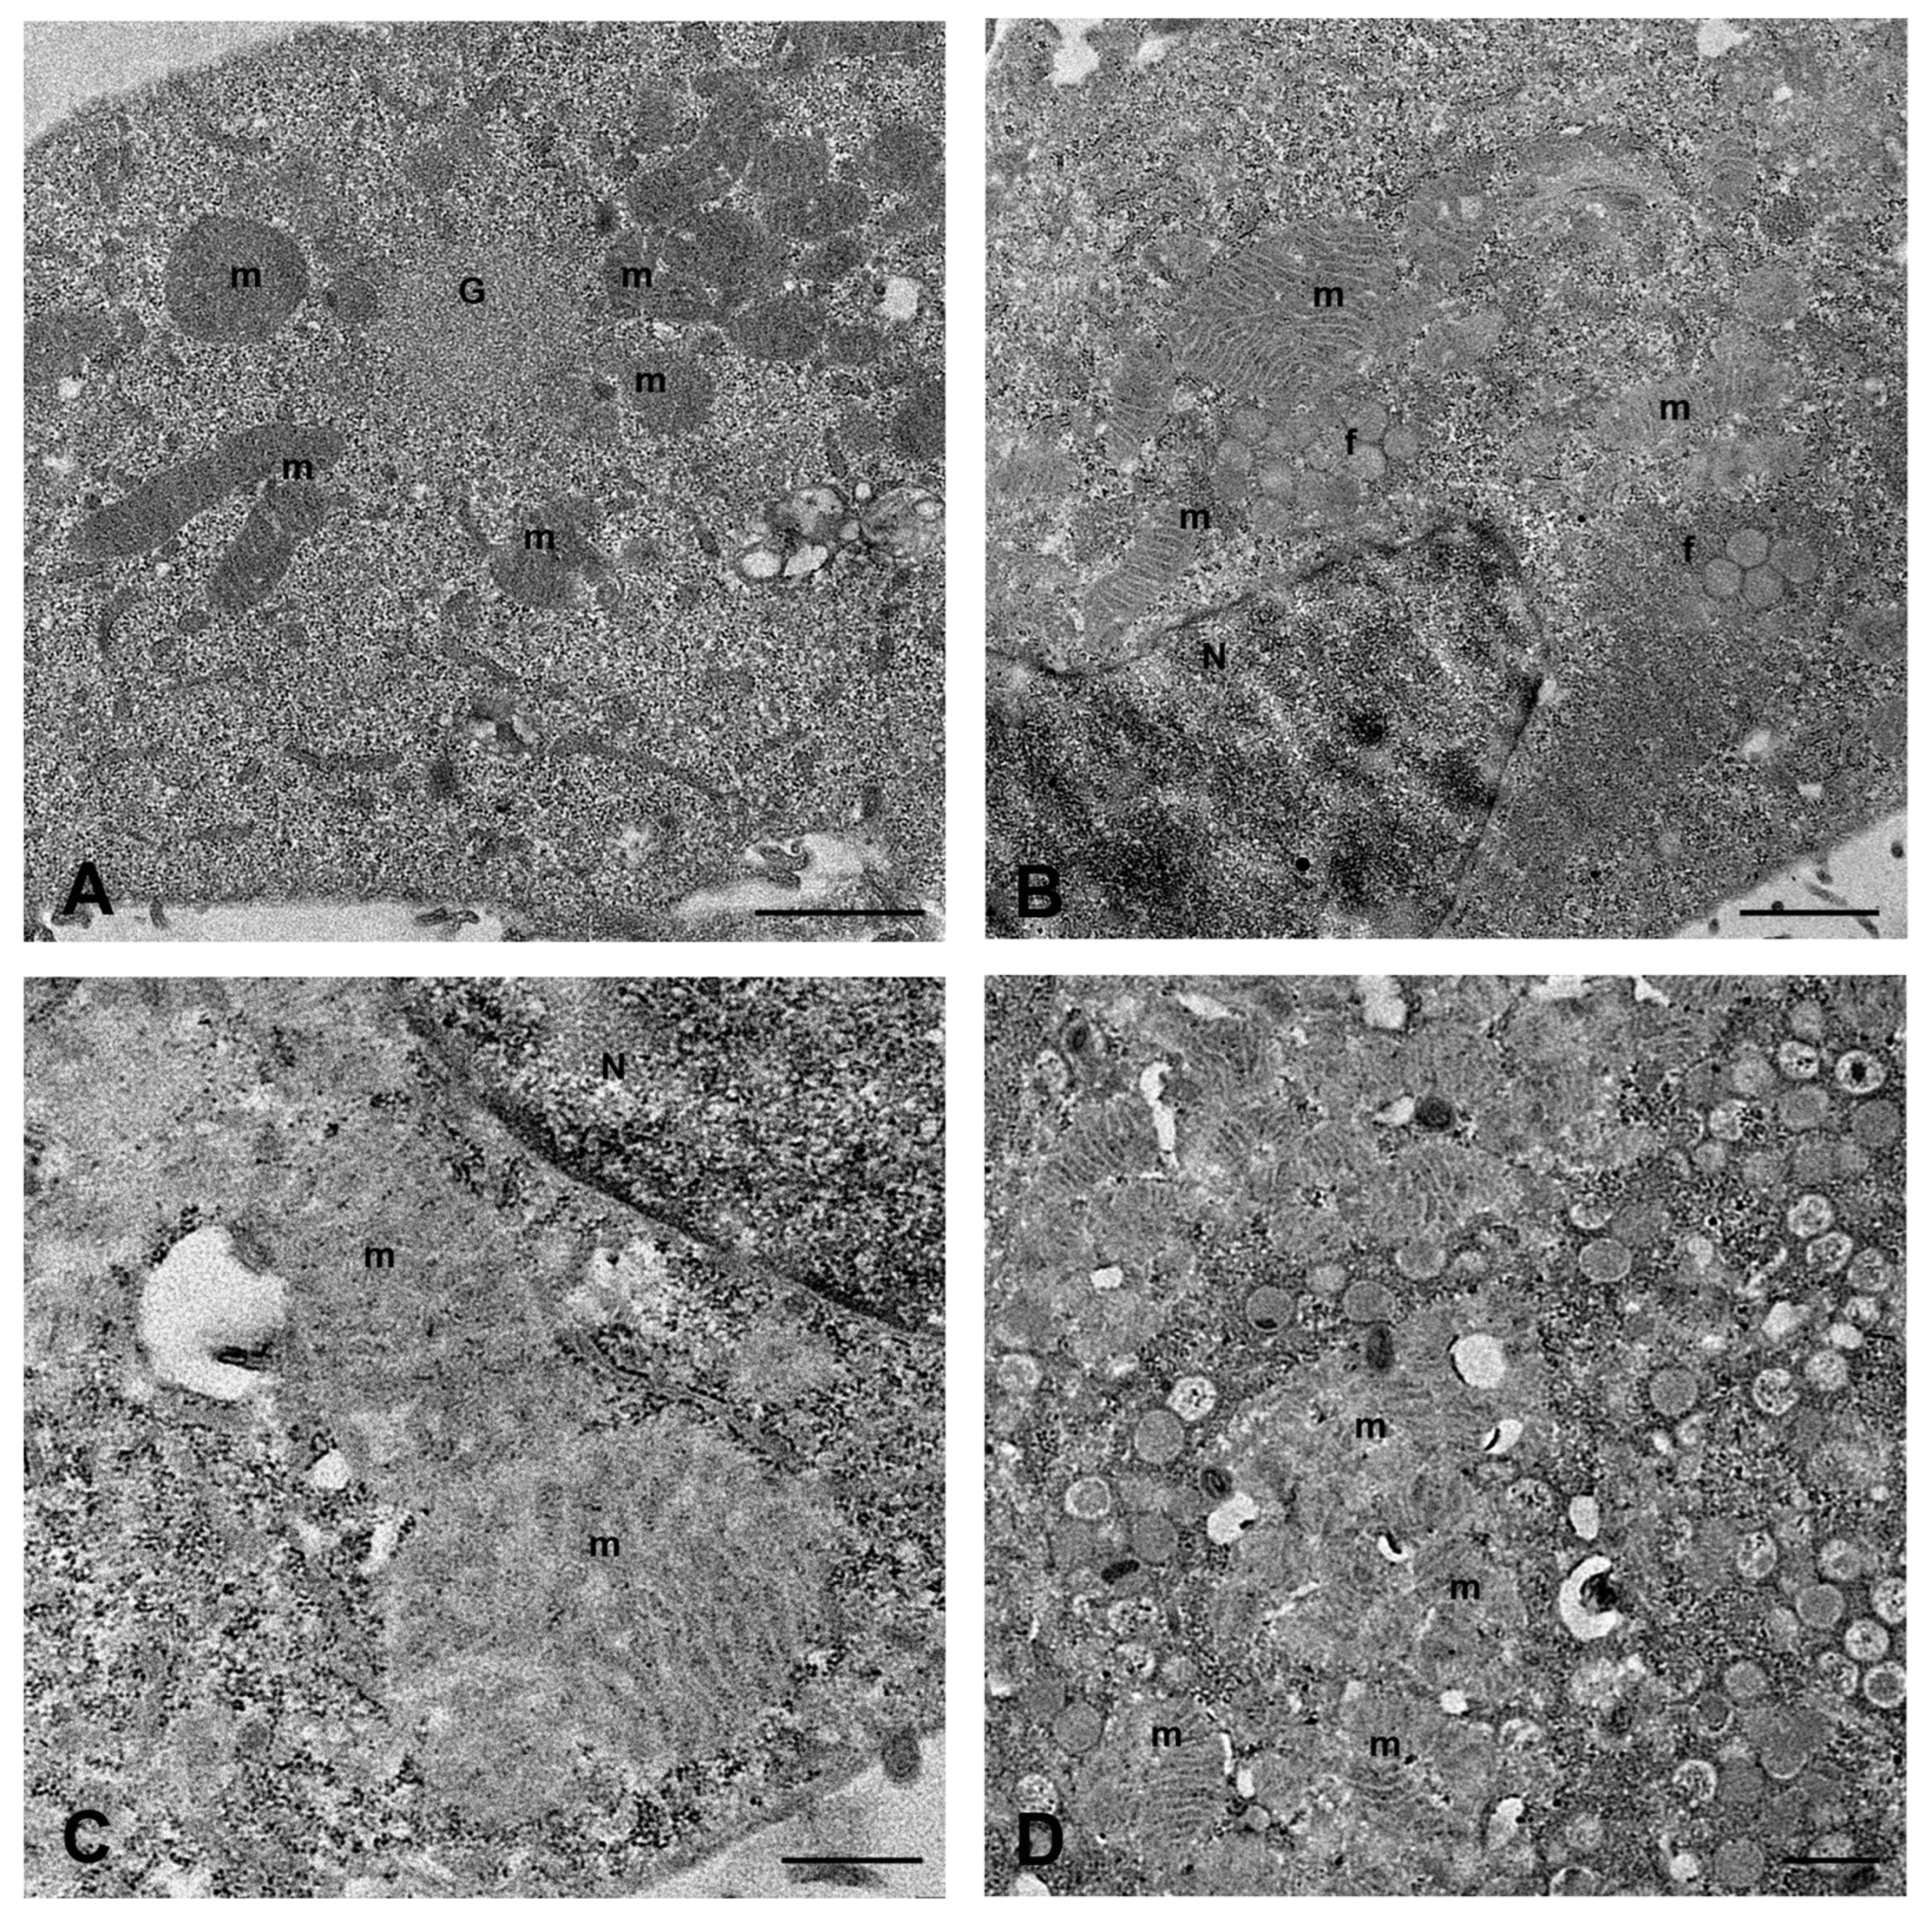

2.1. MPXV Infection of Calu-3 Cells and Analysis of Cell Ultrastructure